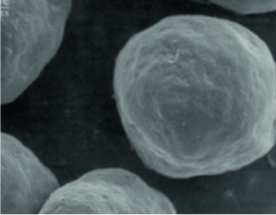

CaHA là một hạt hình cầu mịn, có kích thước đồng đều,

Hình dạng hạt với kích thước nhất định và bề mặt nhẵn cho phép nguyên bào sợi hoạt động tốt và được tối ưu hóa để sản xuất vật liệu tái tạo cho ECM (chất ngoại bào)

(nếu hạt phân tử sắc nhọn và không đều có thể xảy ra phản ứng viêm)

Radiesse

(25~45um/Microsphere)

Sản phẩm A

(30~60um/Crystal)

Sản phẩm B

(20~80um/không đều)